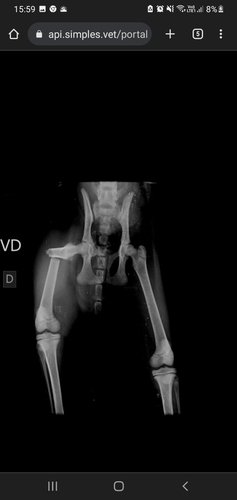

Eu sou a Luana dona da Jasmin, ela sofreu um acidente em casa, a tábua de passar roupa caiu em sua perna ocasionando que quebrou o seu fêmur. Peço a ajuda de vocês pois estou desesperada ela precisa ser operada o quanto antes.Será necessário placa ou gaiola em sua perna. No momento não estou tendo condições para arcar com essa situação.